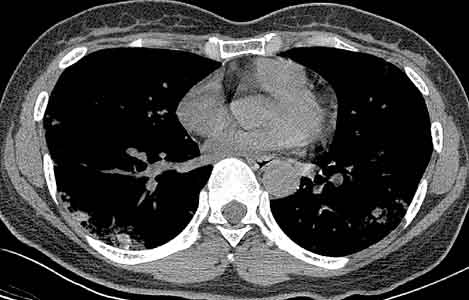

患者女性,43岁,肝癌tace治疗后出现胸闷不适.

请分析肺部改变的成因及可能的诊断.

动静脉瘘,栓塞剂经瘘口进入肝静脉--下腔静脉--右心房--右心室--肺动脉--沉积于肺内.

原发性肝癌进行栓塞治疗时,若肝动脉造影显示肿瘤侵犯肝静脉,且有明显的肝动静脉瘘,则使用碘油乳剂就不妥当,因为大量碘油可通过瘘道进入肺部,引起肺栓塞的并发症。